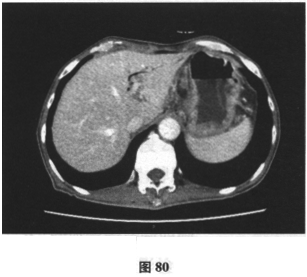

患者男,71岁,因“反复腹胀、纳差6个月,加重伴尿色加重1周余”入院。患者6月前开始肝中上腹胀,进食后加重伴纳差,就诊后予保护胃黏膜治疗症状无缓解。近一月来患者腹胀、纳差较前加重,门诊行胃镜及活检检查示慢性中度萎缩性胃炎伴肠化生,呼气试验示Hp(+),予三联方案(兰索拉唑、左氧氟沙星、克拉霉素)进行Hp根除治疗(该患者青霉素皮试+),停药4周后复查呼气试验示仍(+),调整抗生素后予四联疗法(奥美拉唑、左氧氟沙星、果胶铋、克拉霉素)继续根除治疗,但服药疗程未结束时患者腹胀、纳差加重,伴恶心、呕吐,尿色如浓茶样,伴皮肤黄染,于门诊查肝功能示总胆红素113.7μmol/L,结合胆红素64.5μmol/L,ALT110U/L,AST72U/L,尿常规:胆红素(++)。近2个月体重减轻7.5kg。患者既往于2年前有“肺大疱手术”史,有高血压史6月余,血压最高150/90mmHg,未规律服药。查体:神清,精神尚可,体型消瘦,皮肤巩膜明显黄染,未见肝掌、蜘蛛痣,腹软,无压痛,未及包块,双下肢无水肿。腹部B超未见异常。提示患者进一步检查示肝炎病毒指标、自身抗体均阴性。上腹部增强CT示:胆囊炎,肝内胆管稍扩张(图80),胰腺饱满(图81、图82),肠系膜、后腹膜淋巴结肿大(图83)。胸片显示患者肺部有术后金属物质。根据下面的检查提示,患者可能的诊断是什么?应进一步行何种检查()